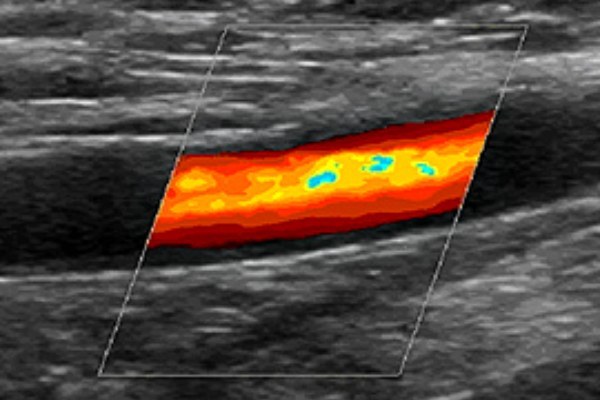

Дуплексное ангиосканирование, или УЗДС, отличается от первого наличием возможностей цветного картирования, позволяющего дополнительно определять направленность тока крови. Потоки, следующие в разных направлениях, приобретают различные цвета, что является для специалиста неоценимой информацией, дающей возможность комплексно определять показатели состояния сосудов.

При исследовании используются разные режимы УЗИ системы нижней полой вены. Например, режим цветного допплеровского сканирования (ЦДС) позволяет дать оценку состояния просвета, выявить наличие зоны патологического кровотока.

Этот вариант УЗИ имеет две составляющие – классическая допплерометрия и в дуплексном режиме с цветовым картированием. Кроме определения структуры сосуда, скорости кровотока, УЗДС вен нижних конечностей позволяет определить направление потоков крови, которые под действием ультразвука получают разное цветовое окрашивание.

Нормальный кровяной поток направляется из поверхностных вен в глубокие. Во время триплексного сканирования (триплекса) с цветным картированием кровоток окрашен в синий цвет.

Если имеется варикоз, нарушается работа венозных клапанов, что способствует обратному току крови. Как следствие, кровоток на мониторе будет красного цвета.

Проводится с импульсным допплером, что делает возможным получение цветного 3D изображения. Кровоток в артериях показывается красным, в венах – синим цветом. Интенсивность окрашивания зависит от скорости передвижения крови.